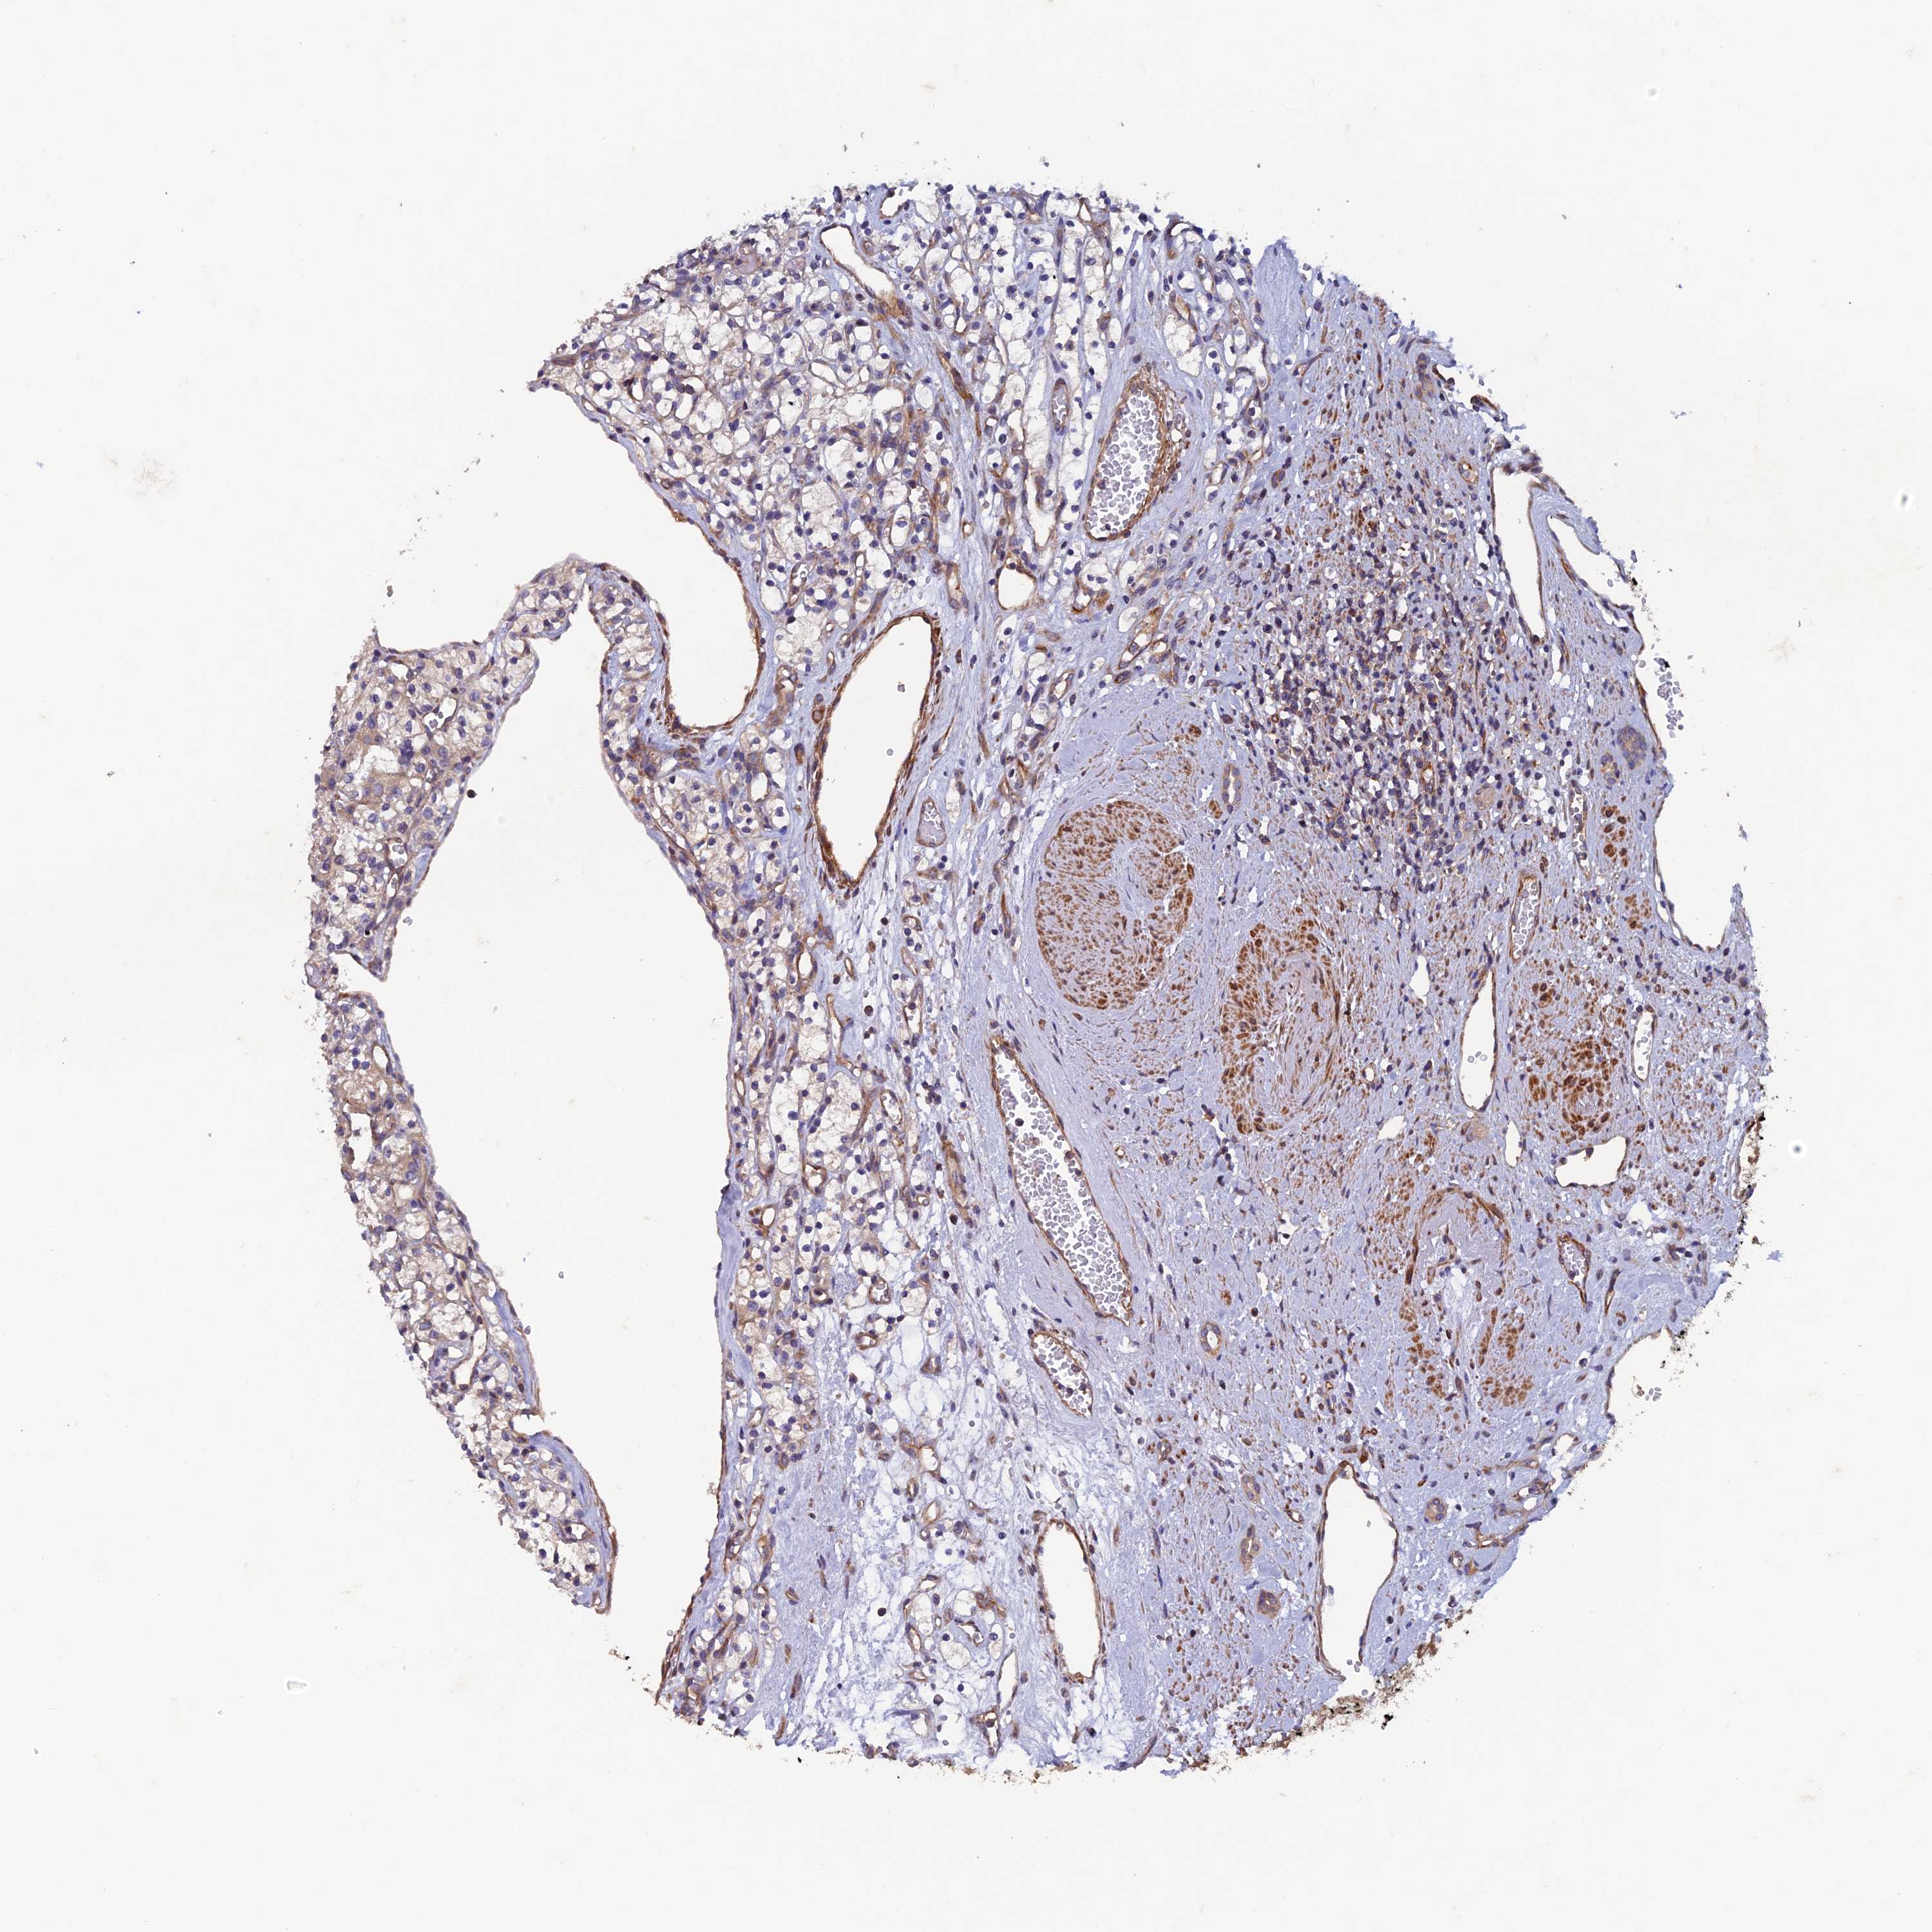

KIDNEY RENAL CLEAR CELL CARCINOMA (VALIDATION) - Interactive survival scatter ploti

The Survival Scatter plot shows the clinical status (i.e. dead or alive) for all individuals in the patient cohort, based on the same data that underlies the corresponding Kaplan-Meier plots. Patients that are alive at last time for follow-up are shown in blue and patients who have died during the study are shown in red.

The x-axis shows the expression levels (FPKM) of the investigated gene in the tumor tissue at the time of diagnosis. The y-axis shows the follow-up time after diagnosis (years). Both axes are complimented with kernel density curves demonstrating the data density over the axes. The top density plot shows the expression levels (FPKM) distribution among dead (red) and alive patients (blue). The right density plot shows the data density of the survived years of dead patients with high and low expression levels respectively, stratified using the cutoff indicated by the vertical dashed line through the Survival Scatter plot. This cutoff is automatically defined based on the FPKM cutoff that minimizes the p-score. The cutoff can be changed by dragging the vertical line or by entering a cutoff value in the square labeled "Current cut-off".

Under the Survival Scatter plot the p-score landscape (black curve; left axis) is shown together with dead median separation (red curve; right axis). Dead median separation is the difference in median mRNA expression between patients who have died with high and low expression, respectively. It is calculated as follows: median FPKM expression of dead patients with high expression - median FPKM expression of dead patients with low expression. This is intended to aid the user in visually exploring custom cutoffs and the associated p-scores and dead median separation.

Individual patient data is displayed and can be filtered by clicking on one or more of the category buttons on the top of the page. Categories describing expression level and patient information include: high, low, alive, dead, female, male and tumor stages. The scale of the x-axis can be toggled between linear and log-scale by clicking on the "x log" button. Mouse-over function shows TCGA ID, patient information and mRNA expression (FPKM) for each patient.

& Survival analysisi

Kaplan-Meier plots summarize results from analysis of correlation between mRNA expression level and patient survival. Patients were divided based on level of expression into one of the two groups "low" (under cut off) or "high" (over cut off). X-axis shows time for survival (years) and y-axis shows the probability of survival, where 1.0 corresponds to 100 percent.

NCAPG is not prognostic in Kidney Renal Clear Cell Carcinoma (validation)

Best expression cut offi

Based on the FPKM value of each gene, patients were classified into two groups and association between prognosis (survival) and gene expression (FPKM) was examined. The best expression cut-off refers the FPKM value that yields maximal difference with regard to survival between the two groups at the lowest log-rank P-value. Best expression cut-off was selected based on survival analysis .

When clicking on this number, the vertical dashed line indicating cut-off, the interactive survival plot, and the Kaplan-Meier curve will be adjusted to show results based on the best expression cut-off.

: 3.07

TCGA RNA samplesi

RNA-seq data is reported as average FPKM (number Fragments Per Kilobase of exon per Million reads), generated by the The Cancer Genome Atlas (TCGA) .

Normal distribution across the dataset is visualized with box plots, shown as median and 25th and 75th percentiles. Points are displayed as outliers if they are above or below 1.5 times the interquartile range. FPKM values of the individual samples are presented next to the box plot.

Average pTPM 2.3

Number of samples 100